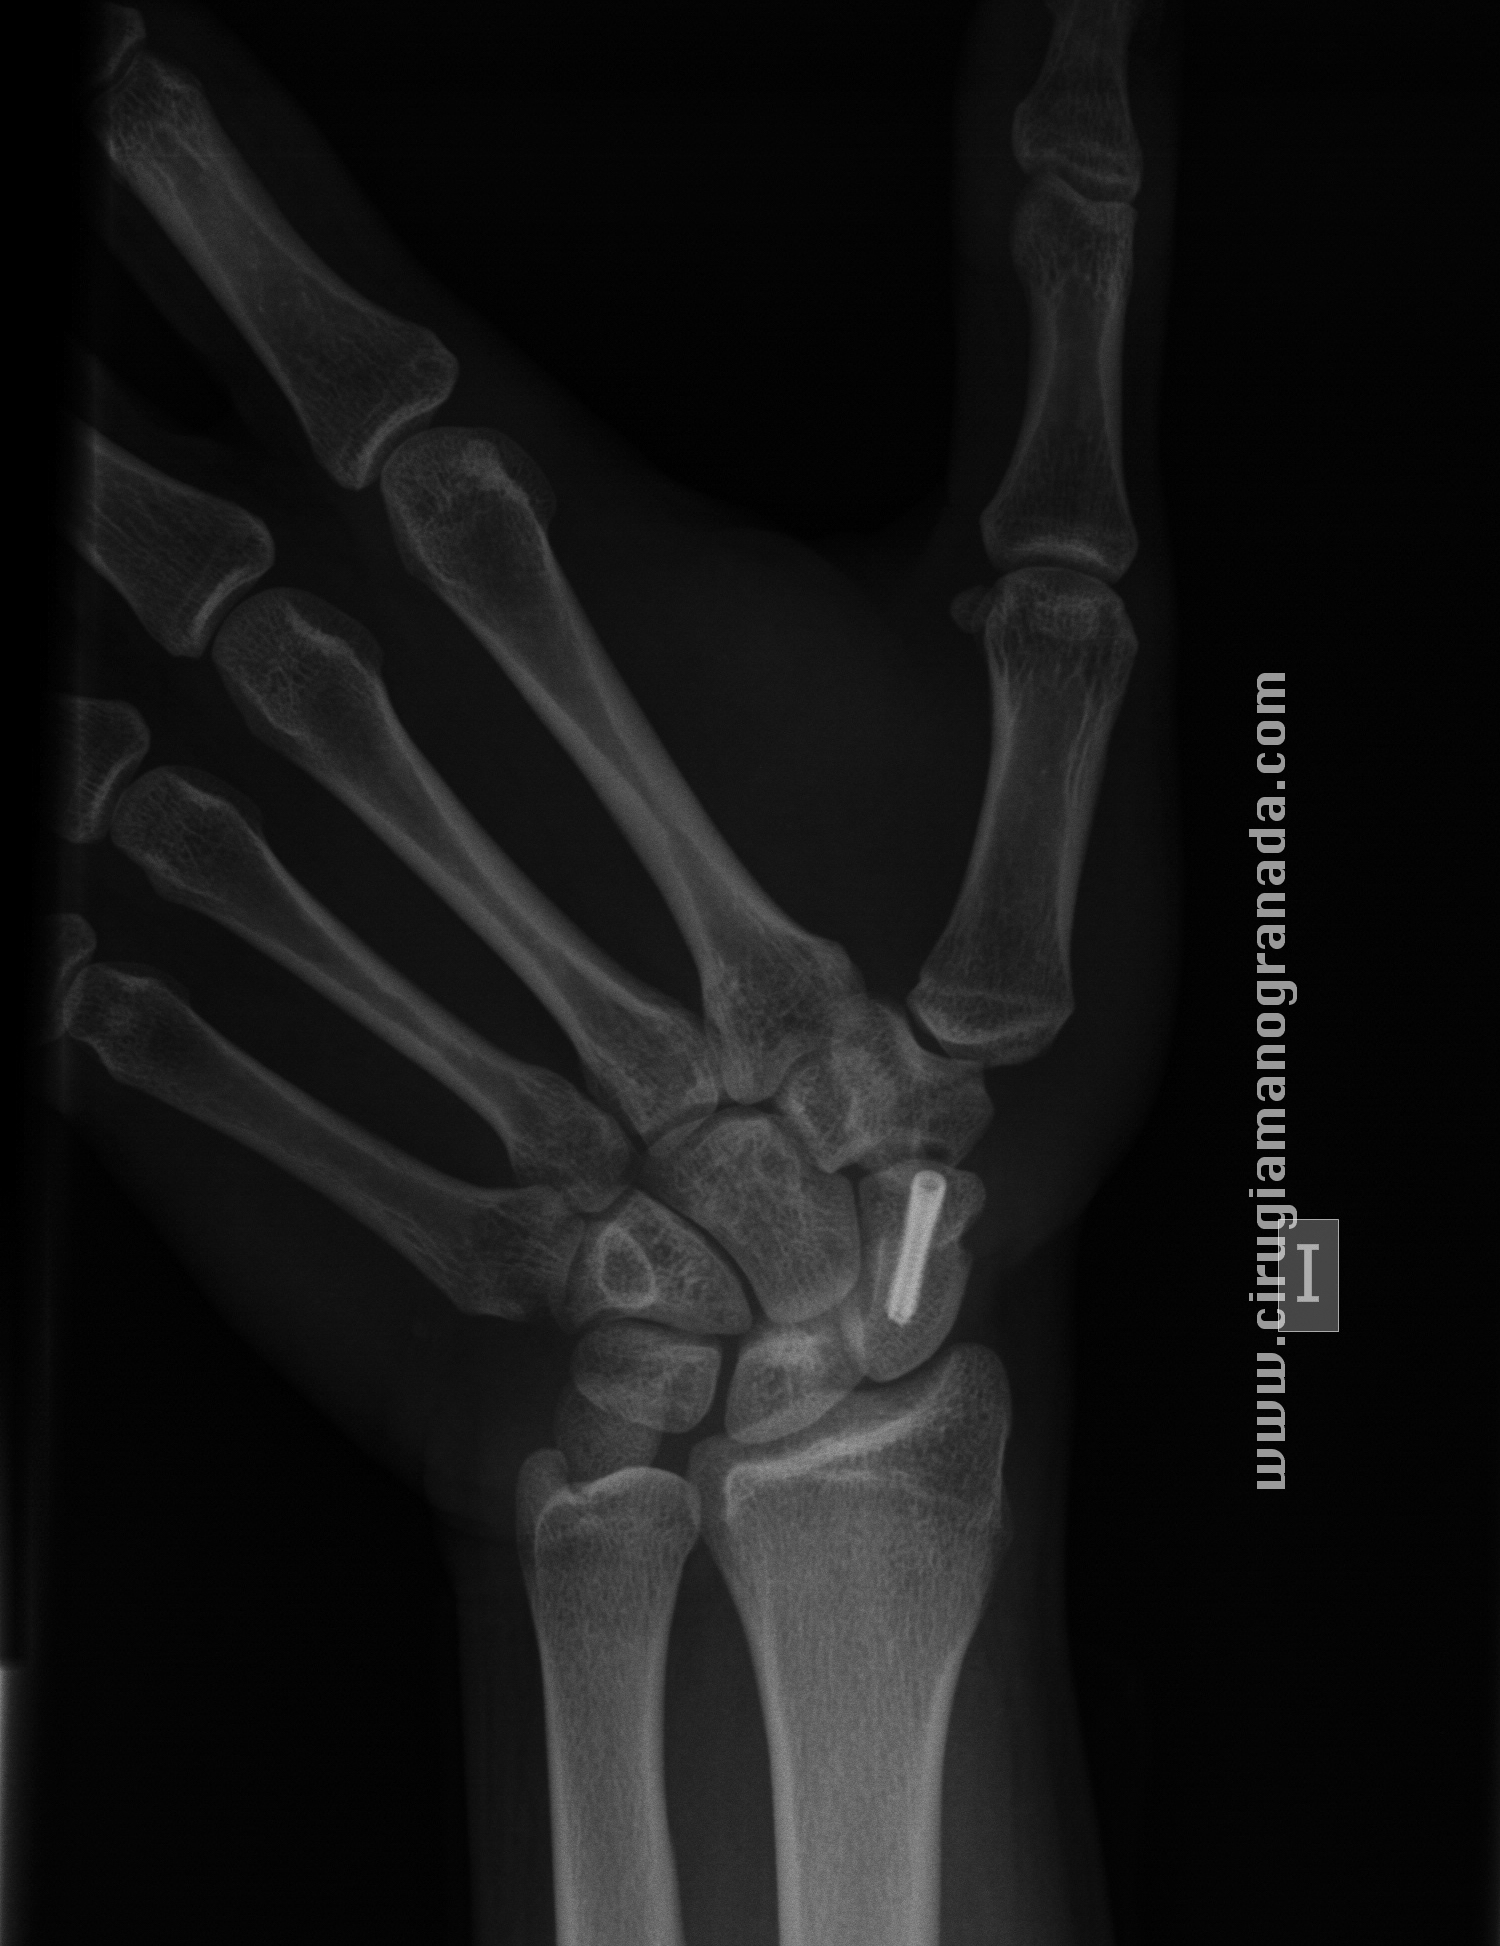

Cirugía de Mano y Traumatología: Pruebas Radiológicas para la fractura

Source: manoytrauma.blogspot.com